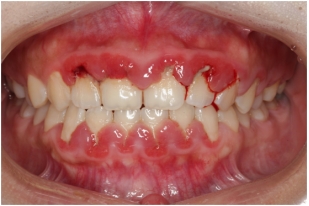

(一)准妈妈的牙周问题

1.牙龈炎:怀孕本身并不会引起牙龈炎,但是由于怀孕后黄体酮和雌激素水平增加,原有的慢性牙龈炎或者牙周炎会加重。所以有些准妈妈会发现孕期刷牙出血增多,有时有自发性的牙龈出血,甚至有些准妈妈的牙齿出现了松动。

妊娠期牙龈炎